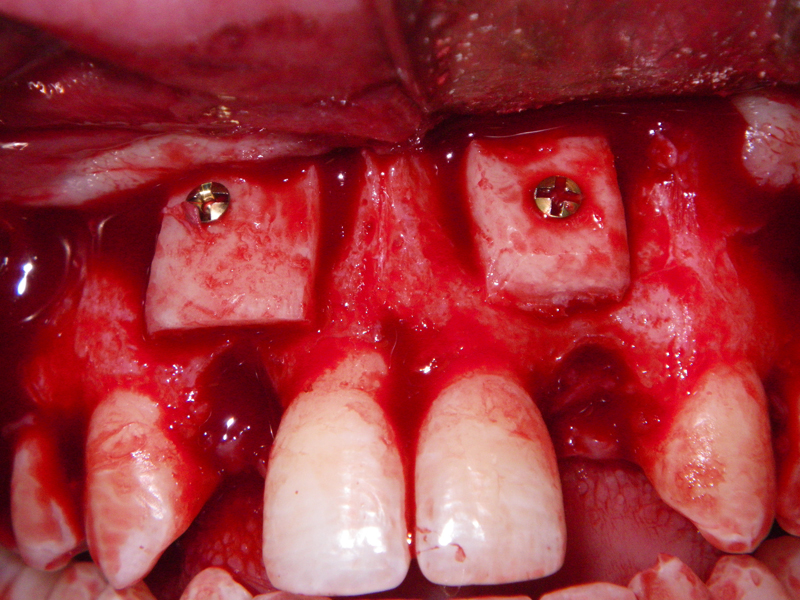

- Alveolar Ridge Augmentation

- Blockgraft